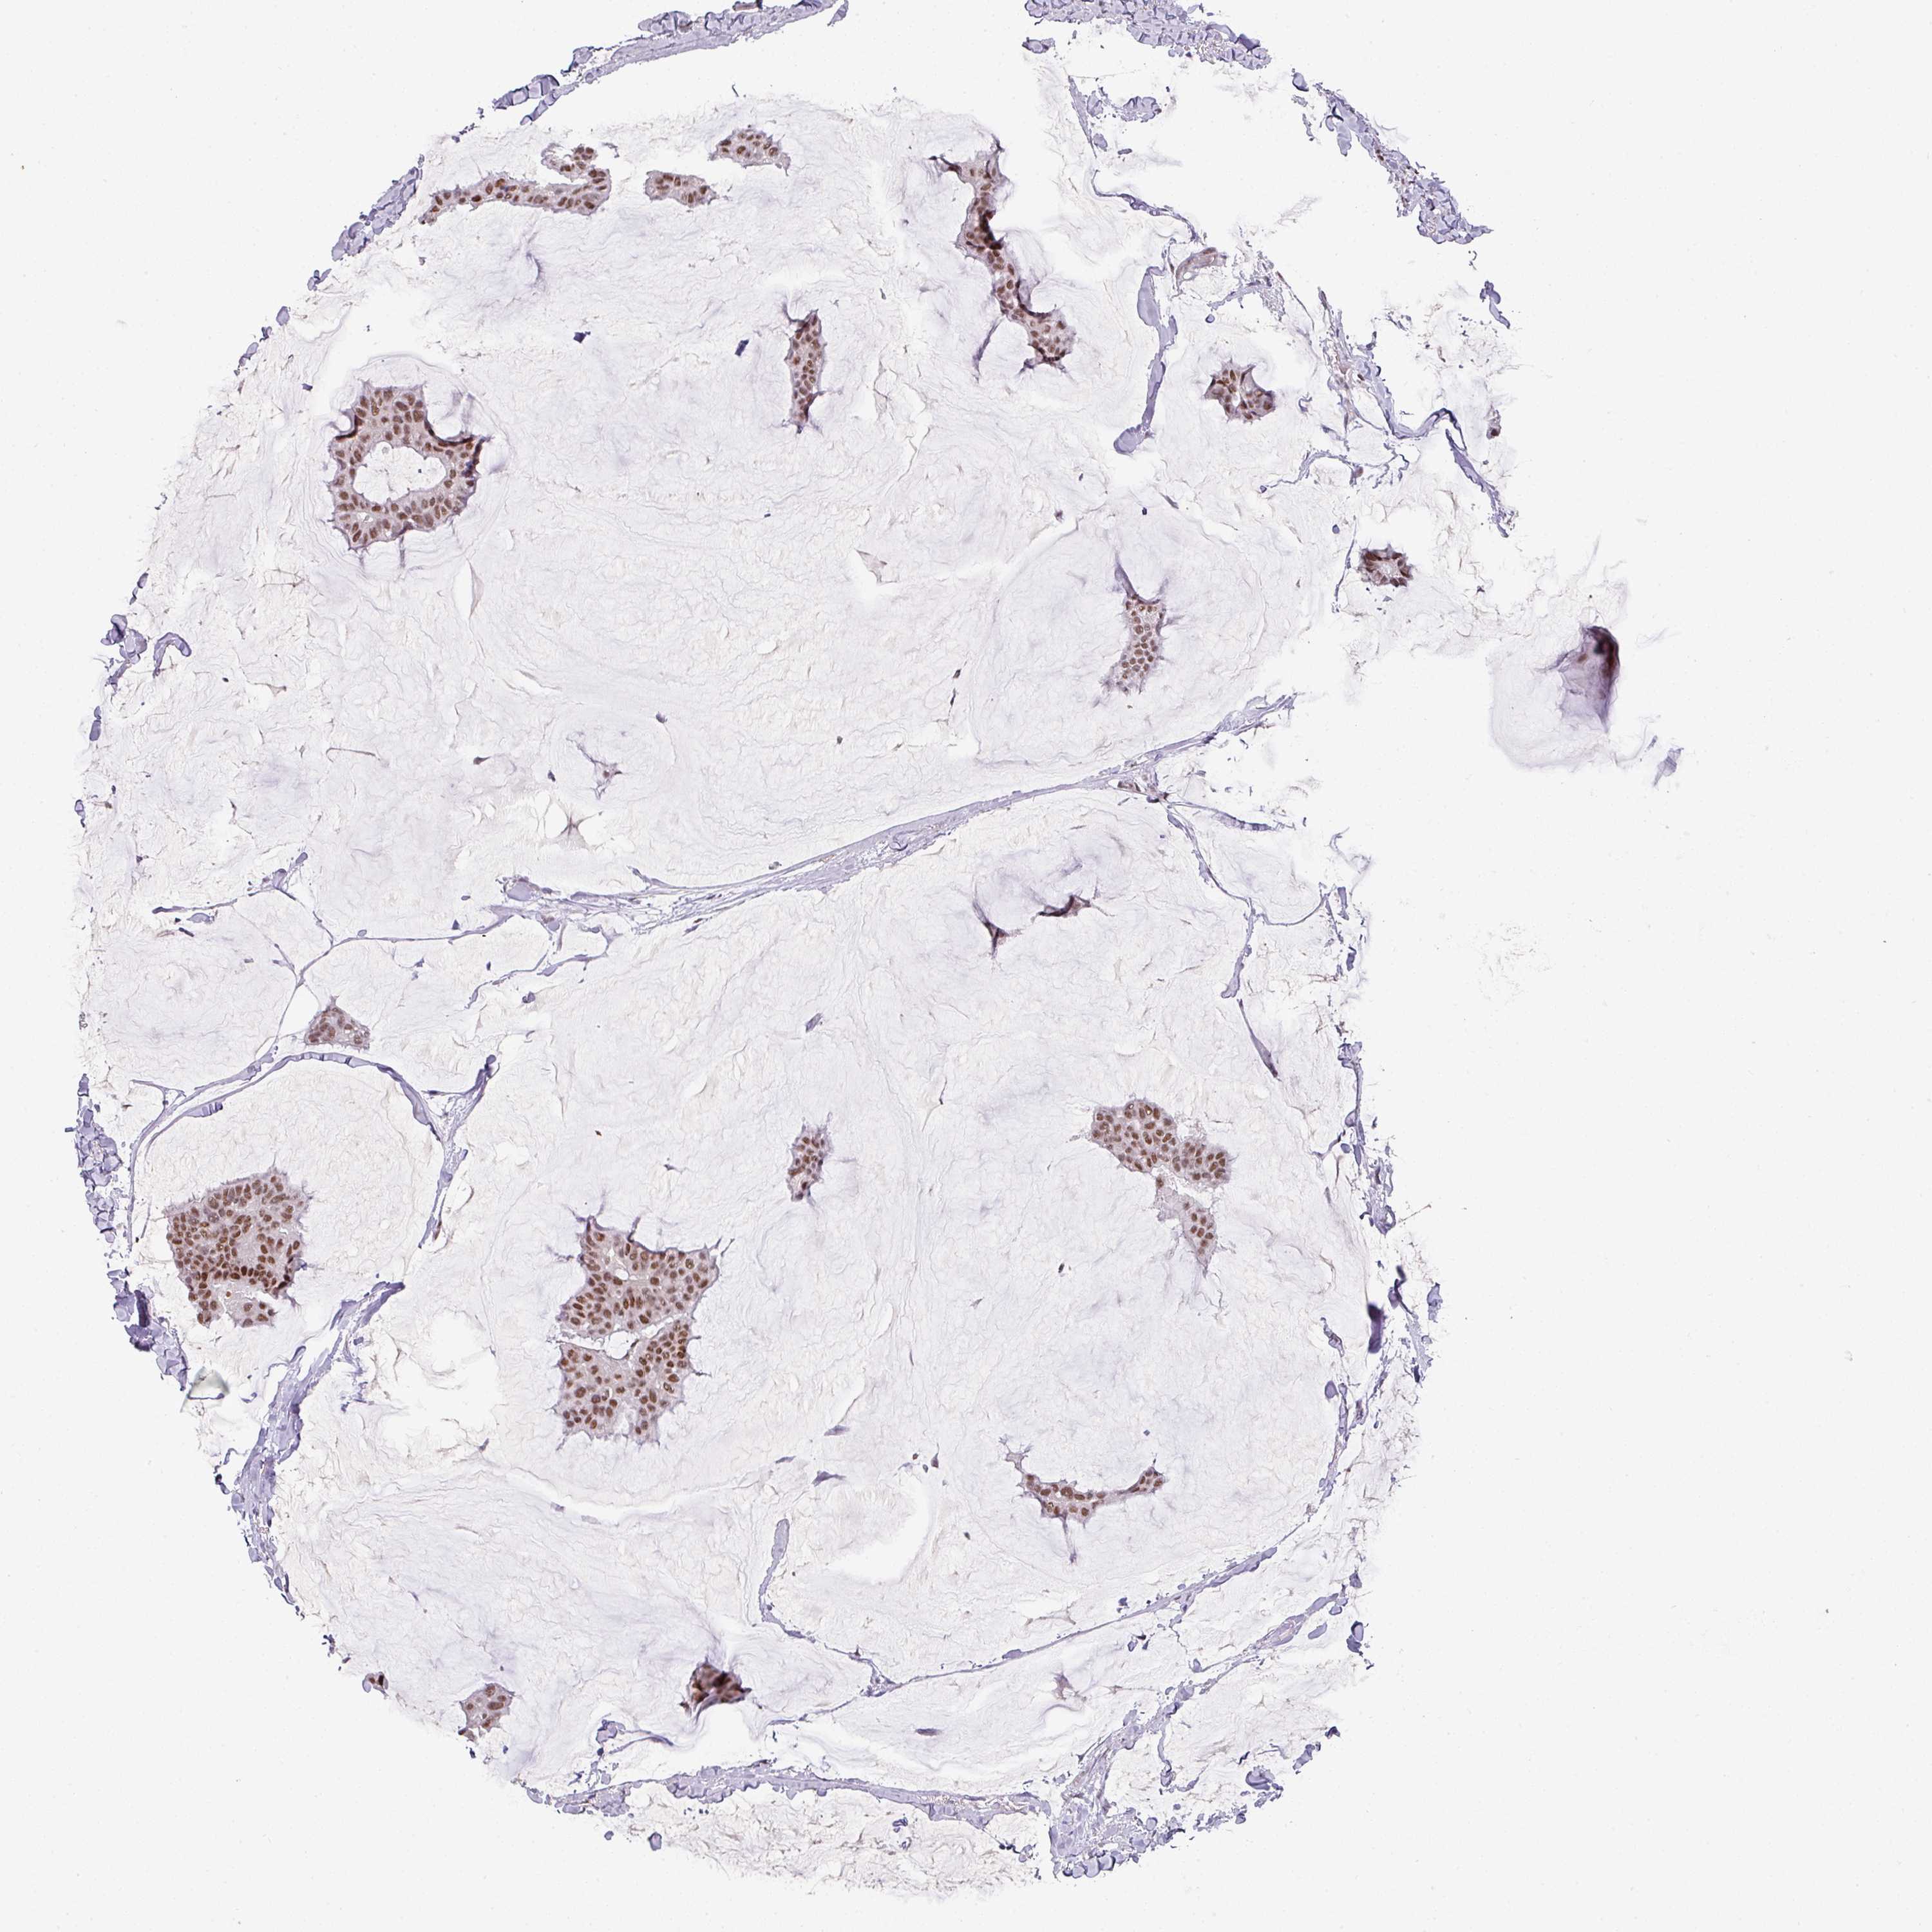

BRCA TCGA BRCA VALIDATION PROTEIN EXPRESSION

Breast cancer

Human cancer